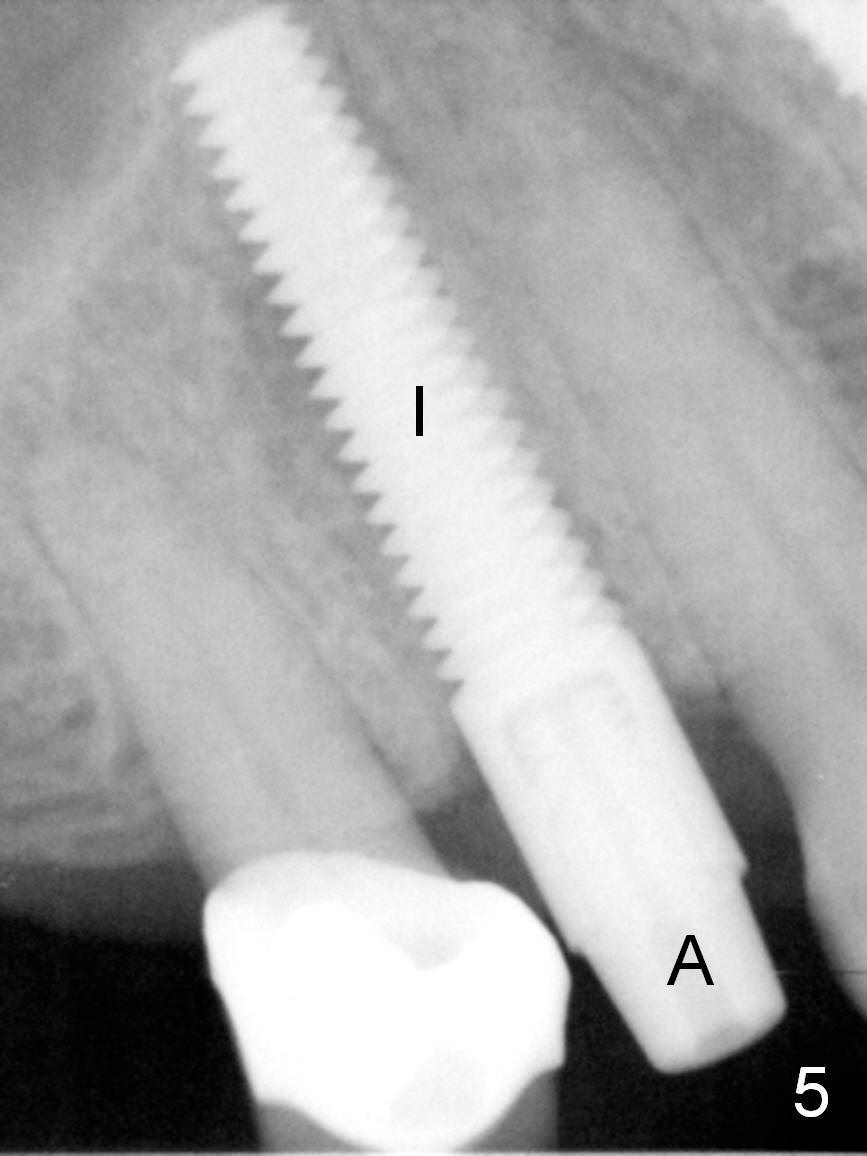

After long discussion, she agrees with extraction and immediate implant. After the extraction, granulation tissue is removed. There is buccal apical fenestration. The socket is treated with Metronidazole. The socket depth is 17 mm, while osteotomy depth is 20 mm (Fig.4). A 4x20 mm tissue-level implant is placed with primary stability (Fig.5,6 I). A short abutment (A) is placed immediately for an immediate provisional. The buccal gap is filled with Osteogen plug. There is no crestal bone loss 3 months postop (Fig.7). The provisional stays in place with occlusal perforation. The gingiva is healthy 5.5 months post cementation (Fig.8).